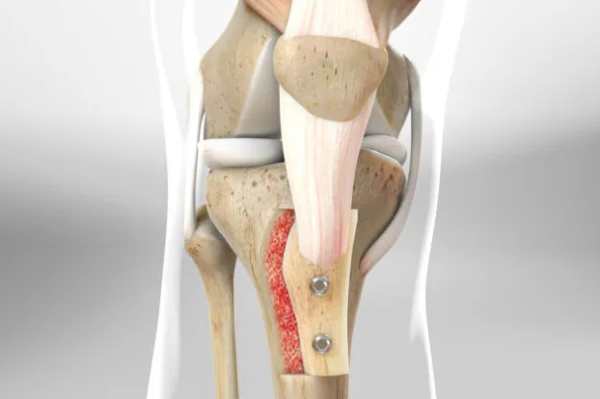

(2)韧带重建

取自体肌腱(如半腱肌)或人工韧带,在股骨侧钻孔固定,另一端缝合至髌骨内侧缘,重建MPFL。

MPFL三联手术过程

基础步骤同二联:先完成MPFL重建,固定股骨和髌骨侧。

(1)附加结构修复

(2)髌骨外侧支持带松解

通过关节镜或小切口松解紧张的外侧支持带,减少髌骨外侧压力。

(3)胫骨结节内移

若存在胫骨结节外偏,需截骨内移并固定,调整髌骨力线。

(4)综合调整

在关节镜监视下,动态测试髌骨稳定性,确保无脱位倾向。